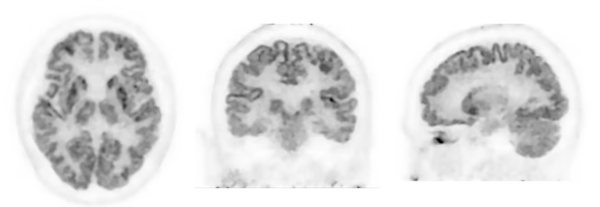

写真:頭部FDG-PET画像

(データご提供:近畿大学高度先端総合医療センターPET分子イメージング部 様)